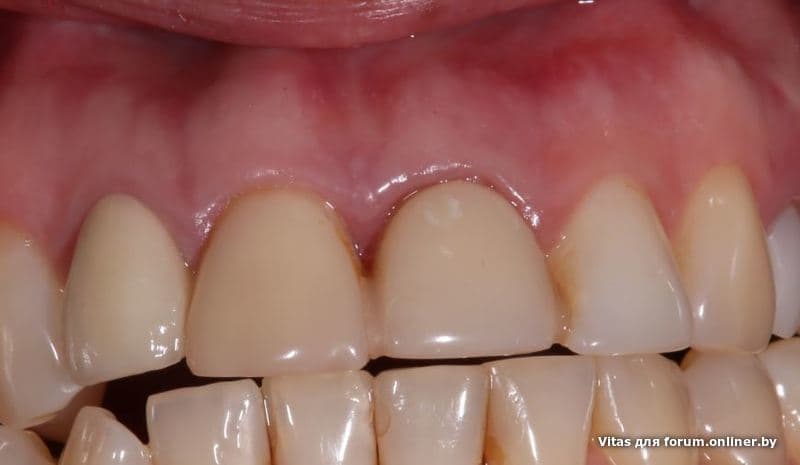

Угадаете где имплант?